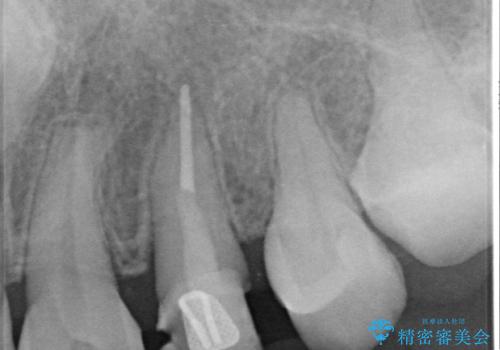

開始前

左:虫歯を除去したところ。遠心が歯ぐきより深い状態です。中:そのままかぶせようとすると、遠心が歯ぐきが腫れやすい状態です。右:エクストリュージョンをしたことで、遠心の歯ぐきの腫れが収まっていることがわかります。